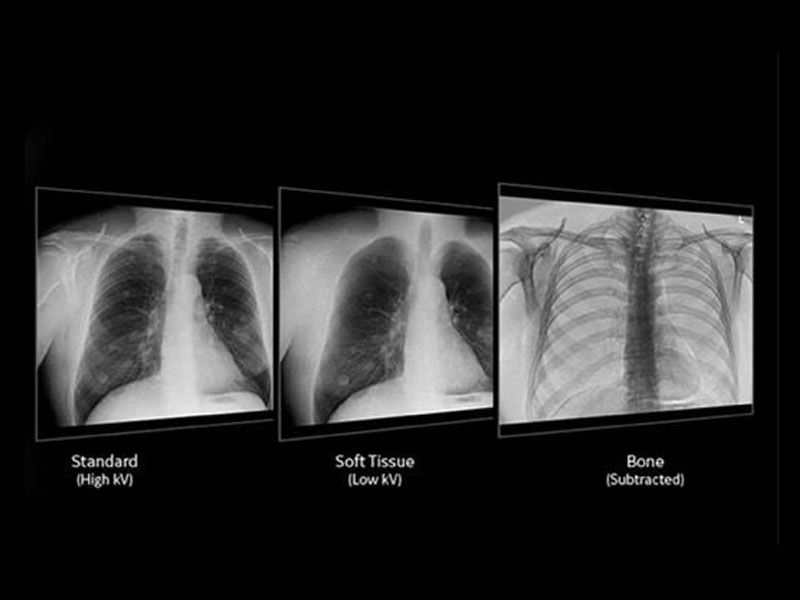

Advanced applications and IQ

Enable radiologists to consistently see more details and provide quality diagnosis